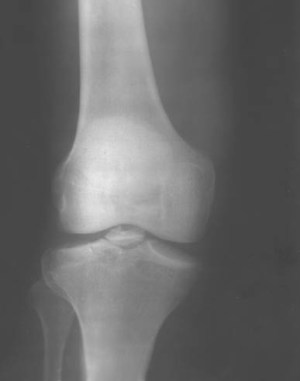

На рентгенограмме чаще всего отмечается один осколок, хотя в некоторых случаях их может быть до 7, хотя такое встречается очень редко.

Очень часто такое состояние принимается за какое-то другое заболевание, особенно в случае, когда боли в колене появились после травмы. Так, например, некоторые списывают это на сильный ушиб, растяжение связок и другие мелочи. Но такая невнимательность нередко приводит довольно тяжёлым последствиям. Поэтому при обследовании очень важно не только сделать рентгенологическое исследование, но и тщательно собрать анамнез жизни пациента и предшествующей болям травмы. Причём проявляться данная проблема может и в локтевом суставе.

Диагностика суставной мыши обычно включает физический осмотр, а также визуализирующие методы, такие как рентгенография, магнитно-резонансная томография (МРТ) или ультразвуковое исследование. Эти методы помогают выявить наличие свободных фрагментов в суставной полости и оценить состояние окружающих тканей.